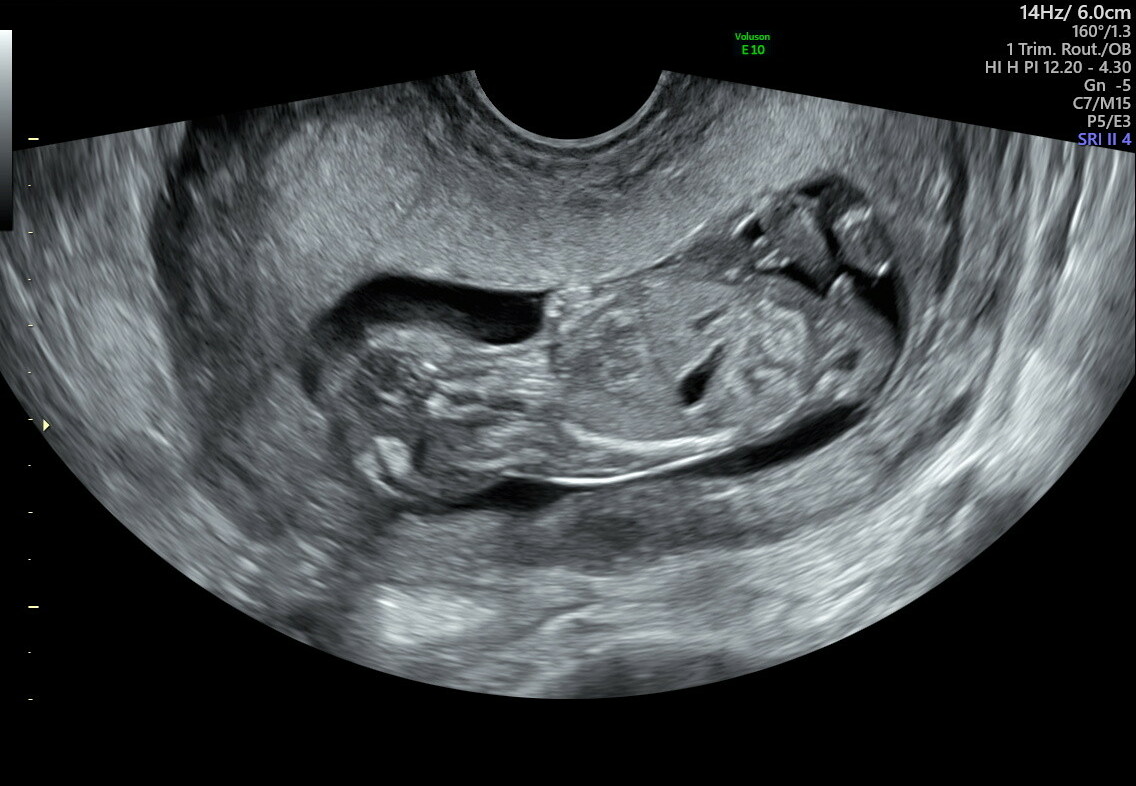

13+1

nå ble jo det meste sjekka I forrige uke, men litt nøyere denne gangen og ingenting å påpeke nå heller! Alt er tipp topp, og det er mest sansynlig en lillebror

nuben pekte rett opp denne gangen, hun sier det enda tidlig, men hun er 80% sikker på at det ikke vil endre seg, 20% bare pga det er tidlig enda

Ble ikke så gode bilder denne gangen, da lille ligger langt nede, har bakovervendt livmor (og en del ekstra på kroppen) så innvendig ul ga best innsyn, men der begynner lille å bli litt stor også

Var 12+5 idag,men lille ble målt til 13+1, og termin ble satt til 30/5, får ikke det til å stemme annet enn at dataen regner 40+0 og ikke 40+3, så tror jeg holder på 2/6 frem til oul 28/12, selvom termin egentlig ble satt idag

Siste bilde her er tydelig bilde av nuben